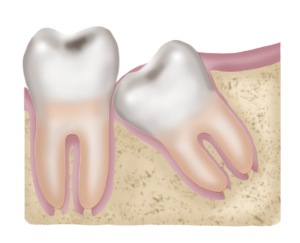

EXODÒNCIA DE CORDALS

Els queixals del seny tenen aquest nom no perquè surten quan posem capteniment… sinó perquè realment poden fer perdre el senderi. Aquests tercers molars habitualment no tenen espai suficient a la boca per erupcionar de manera que es puguin utilitzar per mastegar.

A la part superior, l’os maxil·lar és molt tou i a posterior hi ha estructures musculars on aquests molars surten sense demanar permís i obstaculitzen l’articulació temporo-mandibular. Es molt curiós perquè en aquest nivell el consultant no nota que el problema sigui aquest molar, sinó que noten migranyes i/o dolor a les cervicals o cansament excessiu.

En la part inferior, el consultant sí que experimenta simptomatologia inflamatòria i infecciosa ja que en aquest nivell l’os de la mandíbula pot no deixar que aquest queixal erupcioni i es presenta cobert de geniva i musculatura que el mantenen semi-erupcionat. També poden donar dolor a distància, sobretot a les articulacions inferiors, degut a les relacions a través de meridians i cadenes musculars.

Hi ha un altre problema amb els queixals del seny: és en els casos en els què queden inclosos dins l’os. En aquests casos poden provocar dolors a distància ja que bloquegen el flux energètic d’un meridià d’acupuntura. Aquest tipus de relacions a distància estan molt ben descrites per el Dr. Ernest Adler, pare de la odontologia neurofocal.